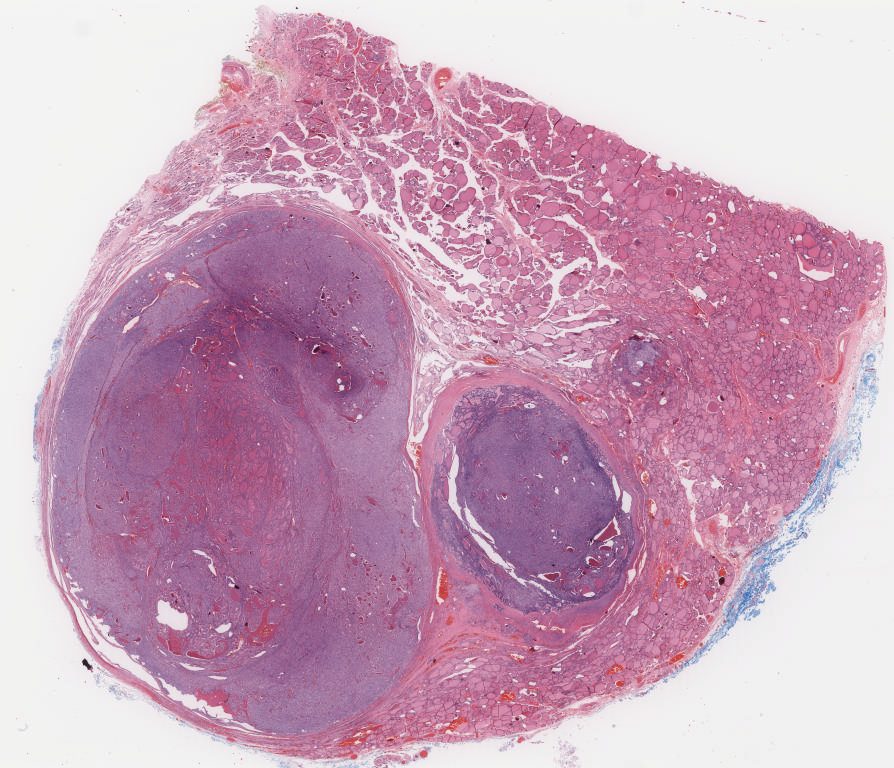

TSN 032.2.svs

101864

x

87434

@

40X